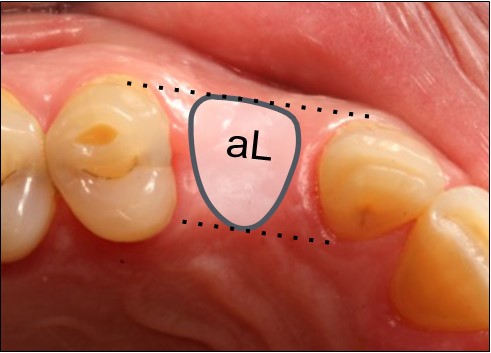

Pasul 1 – Evaluează dimensiunea mezio-distală a spațiului edentat

Evaluarea dimensiunii mezio-distale este importantă pentru a putea identifica dacă spațiul este adecvat pentru a plasa în siguranță un implant.

Evaluarea dimensiunii mezio-distale este importantă pentru a putea identifica dacă spațiul este adecvat pentru a plasa în siguranță un implant.

Această dimensiune se referă, de asemenea, la diametrul maxim al platformei implantului care poate fi plasat în siguranță fără a încălca zona periculoasă. Adică platforma implantului va avea o distanță inter-proximală sigură de cel puțin 1,5 mm față de dinții adiacenți.

Partea 2 – Identifică dimensiunile și forma profilului cervical gingival ideal (Bont personalizat de vindecare)

Utilizează fila de formă anatomică din același grup ca pentru dintele lipsă (de ex. Premolar).

Poți utiliza alternativ cele trei dimensiuni diferite (mici, medii sau mari) până când identifici dimensiunea potrivită. Mărimea ideală este cea cu aceeași dimensiune buco-linguală cu cea a coroanei care urmează să fie plasată (biotip de țesut moale gros), sau o dimensiune mai mică (biotip de țesut moale subțire).

Pune o notă în diagrama pacientului din fila selectată (de exemplu, pS)

Biotip de țesut moale gros (a)

Biotip de țesut moale gros (a)

Ai ales o dimensiune egală cu cea a porțiunii cervicale a viitoarei proteze.

Biotip de țesut moale subțire (b)

Ai ales o dimensiune mai mică decât cea a porțiunii cervicale a viitoarei proteze.